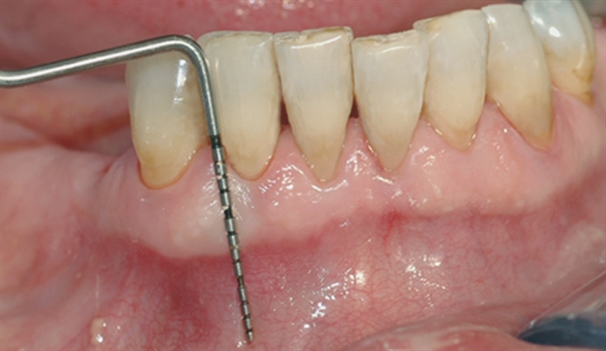

perio stor 2

En undersøkelse med lommeregistrering avdekker likevel et omfattende bentap ved den ene tannen.

perio stor 3

Instrumentet er her lagt utenfor tannkjøttet for å vise hvor stort festetapet egentlig er.